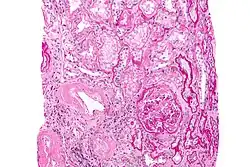

Ursächlich für die Erkrankung sind monoklonale freie Leichtketten (vom Typ Lambda (λ) oder Kappa (κ)) oder deren Fragmente, die von einer Form bösartig veränderter B-Zellen (den sogenannten monoklonalen Plasmazellen) produziert und ausgeschieden werden. Durch Fehlfaltung neigen diese zur Aggregation. Diese Aggregate bilden bei der AL-Amyloidose Fibrillen, die sich meist extrazellulär in fast allen Organen ablagern können.[9][10] Dadurch wird deren Funktion zunehmend beeinträchtigt, was zu dem typischen Erscheinungsbild der Krankheit führt (siehe Abschnitt Klinische Erscheinungen). Die Aminosäure-Sequenz und die dreidimensionale Struktur der Leichtketten kann bei betroffenen Patienten beeinträchtigt oder sogar verkürzt sein. Infolgedessen kann es in der dreidimensionalen Struktur zur Ausbildung eines β-Faltblatts und nicht zu der üblichen α-Helix kommen.[11] Diese strukturelle Abnormalität begünstigt die Aggregation und ist von diagnostischer Bedeutung beim Nachweis fehlgefalteter freier Leichtketten mittels Kongorot (siehe Abschnitt Untersuchungsmethoden).[12][13]

Der Kongorotfärbung einer Gewebebiopsie ist hinzuzufügen, dass auch häufig auf Proben der vergangenen 1–2 Jahre zur nachträglichen Anfärbung zurückgegriffen werden kann, soweit solche Proben bereits vorliegen. Zur eindeutigen Diagnose ist eine Biopsie integraler Bestandteil. Bei einem positiven Befund (polarisationsoptische Doppelbrechung in grüner oder rot-gelblicher Farbe), muss das Amyloid (immunhistologisch oder ggf. mittels Massenspektrometrie) typisiert werden um die zugrundeliegende Amyloidose-Form zu bestätigen, da die Kongorotfärbung nicht spezifisch für die AL-Amyloidose ist.[31][32][33]